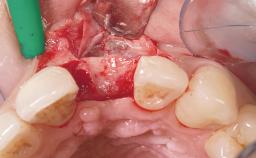

Late Flapless Placement of an Implant in a Maxillary Left Central Incisor Site

Soft Tissue Grafting Simultaneous

Soft Tissue Contour and Volume Slightly compromised